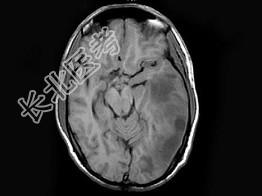

- 单项选择题男,30岁, 寒战,高热伴头痛, 呕吐10天,头颅MRI平扫及增强扫描见颅内不规则环形强化, 应诊断为 ( )

A、化脓性脑膜脑炎并脑脓肿形成

B、结核性脑膜脑炎并结核瘤形成

C、脑膜及颅内转移瘤

D、星形细胞瘤

E、未见异常